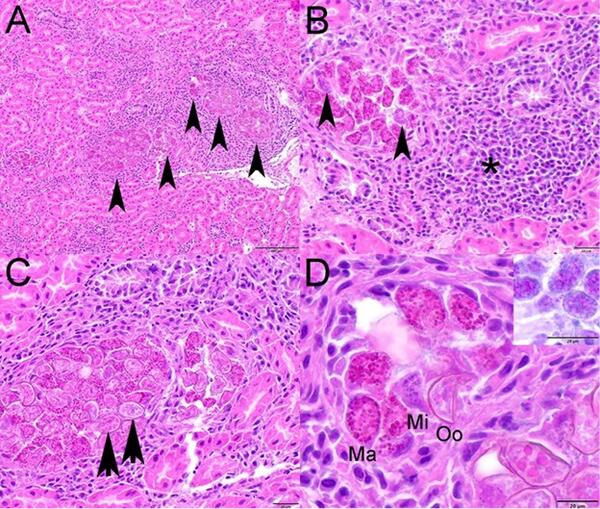

Photomicrographs from a Canada Goose (Branta canadensis) from Ohio, USA.Photomicrographs from a Canada Goose (Branta canadensis) from Ohio, USA. Hematoxylin and eosin stain. (A) Renal tubules are distended with various stages of intraepithelial coccidia (arrowheads) and are surrounded by inflammation. (B) Macrogamonts and fewer microgamonts (arrowheads) expa